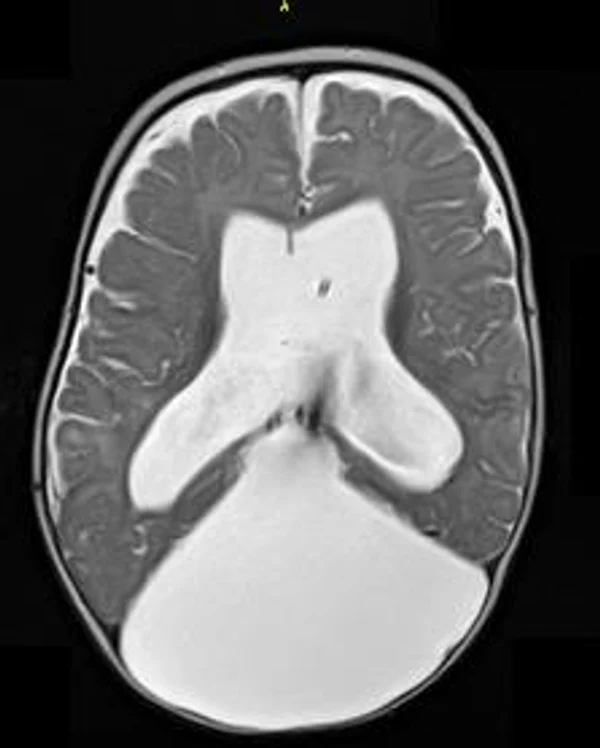

кисты, аномалии Денди-Уокера и др.Операции при внутричерепных кистах. В основном встречаются арахноидальные кисты различных локализаций и кисты сосудистых сплетений боковых желудочков. Пациентам с врождёнными кистами операции проводятся в следующих ситуациях: увеличении объема кисты в динамике, наличии клинических проявлений, компрессии и дислокации мозговых структур, наличии окклюзии ликворных путей. Нами используются 2 способа хирургического лечения кист: эндоскопическая перфорация стенок кист и открытая резекция кист. Открытая резекция кист проводится при ретроцеребеллярных арахноидальных кистах (рис. 2), при арахноидальных кистах межполушарной щели при отсутствии непосредственного контакта их стенок со стенками расширенных желудочков головного мозга и повторного увеличения кист средней черепной ямки после эндоскопической кисто-цистерностомии. Техника операции заключается в проведение краниотомии и максимальном иссечении стенок кист с созданием широкого сообщения кист с субарахноидальным пространством. Эндоскопические операции проводятся при арахноидальных кистах межножковой и пинеальной цистерн, арахноидальных кистах межполушарной щели при тесном контакте их стенок со стенками расширенной желудочковой системы (рис. 3), первично при арахноидальных кистах средней черепной ямки, а также при кистах сосудистых сплетений боковых желудочков. При арахноидальных кистах межножковой цистерны эндоскопически проводится перфорация стенок кисты, сообщая ее с просветом III желудочка и межножковой цистерной – эндоскопическая вентрикуло-кисто-цистерностомия (рис. 4). При арахноидальных кистах пинеальной цистерны проводится перфорация кисты в передне-верхних её отделах с созданием сообщения полости кисты с просветом III желудочка – эндоскопическая кисто-вентрикулостомия. С целью предотвращения облитерации сформированного отверстия иногда в полость кисты под контролем эндоскопа вводится стент перфорированный на протяжении (рис. 5, 6). Эндоскопическая кисто-цистерностомия выполняется при арахноидальных кистах средней черепной ямки. При этом создается широкое сообщение кисты с базальными цистернами. При кистах сосудистых сплетений боковых желудочков проводится их вскрытие в просвет боковых желудочков – эндоскопическая кисто-вентрикулостомия. При множественных кистах проводится их хирургическое сообщение между собой – интеркистосмия